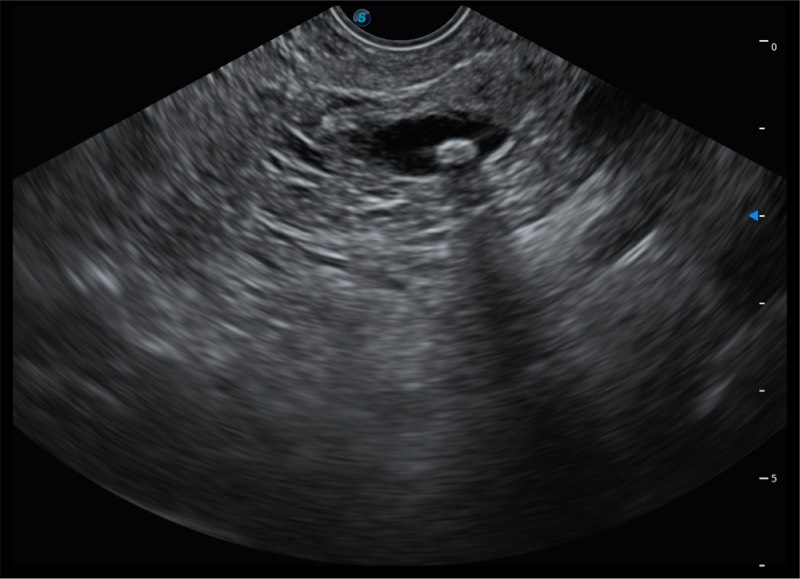

搭载百万级CMOS成像技术

及自主研发凸阵换能器,

可呈现优质的内镜和超声画面

基于二十年的超声技术积累,开立提供了最新一代的独立超声主机,在提供高质量图像的同时满足多学科使用。具备常见多普勒技术并提供弹性成像、声学造影等高端影像技术。新一代传感器具有更强的抗干扰能力并减少图像伪影。